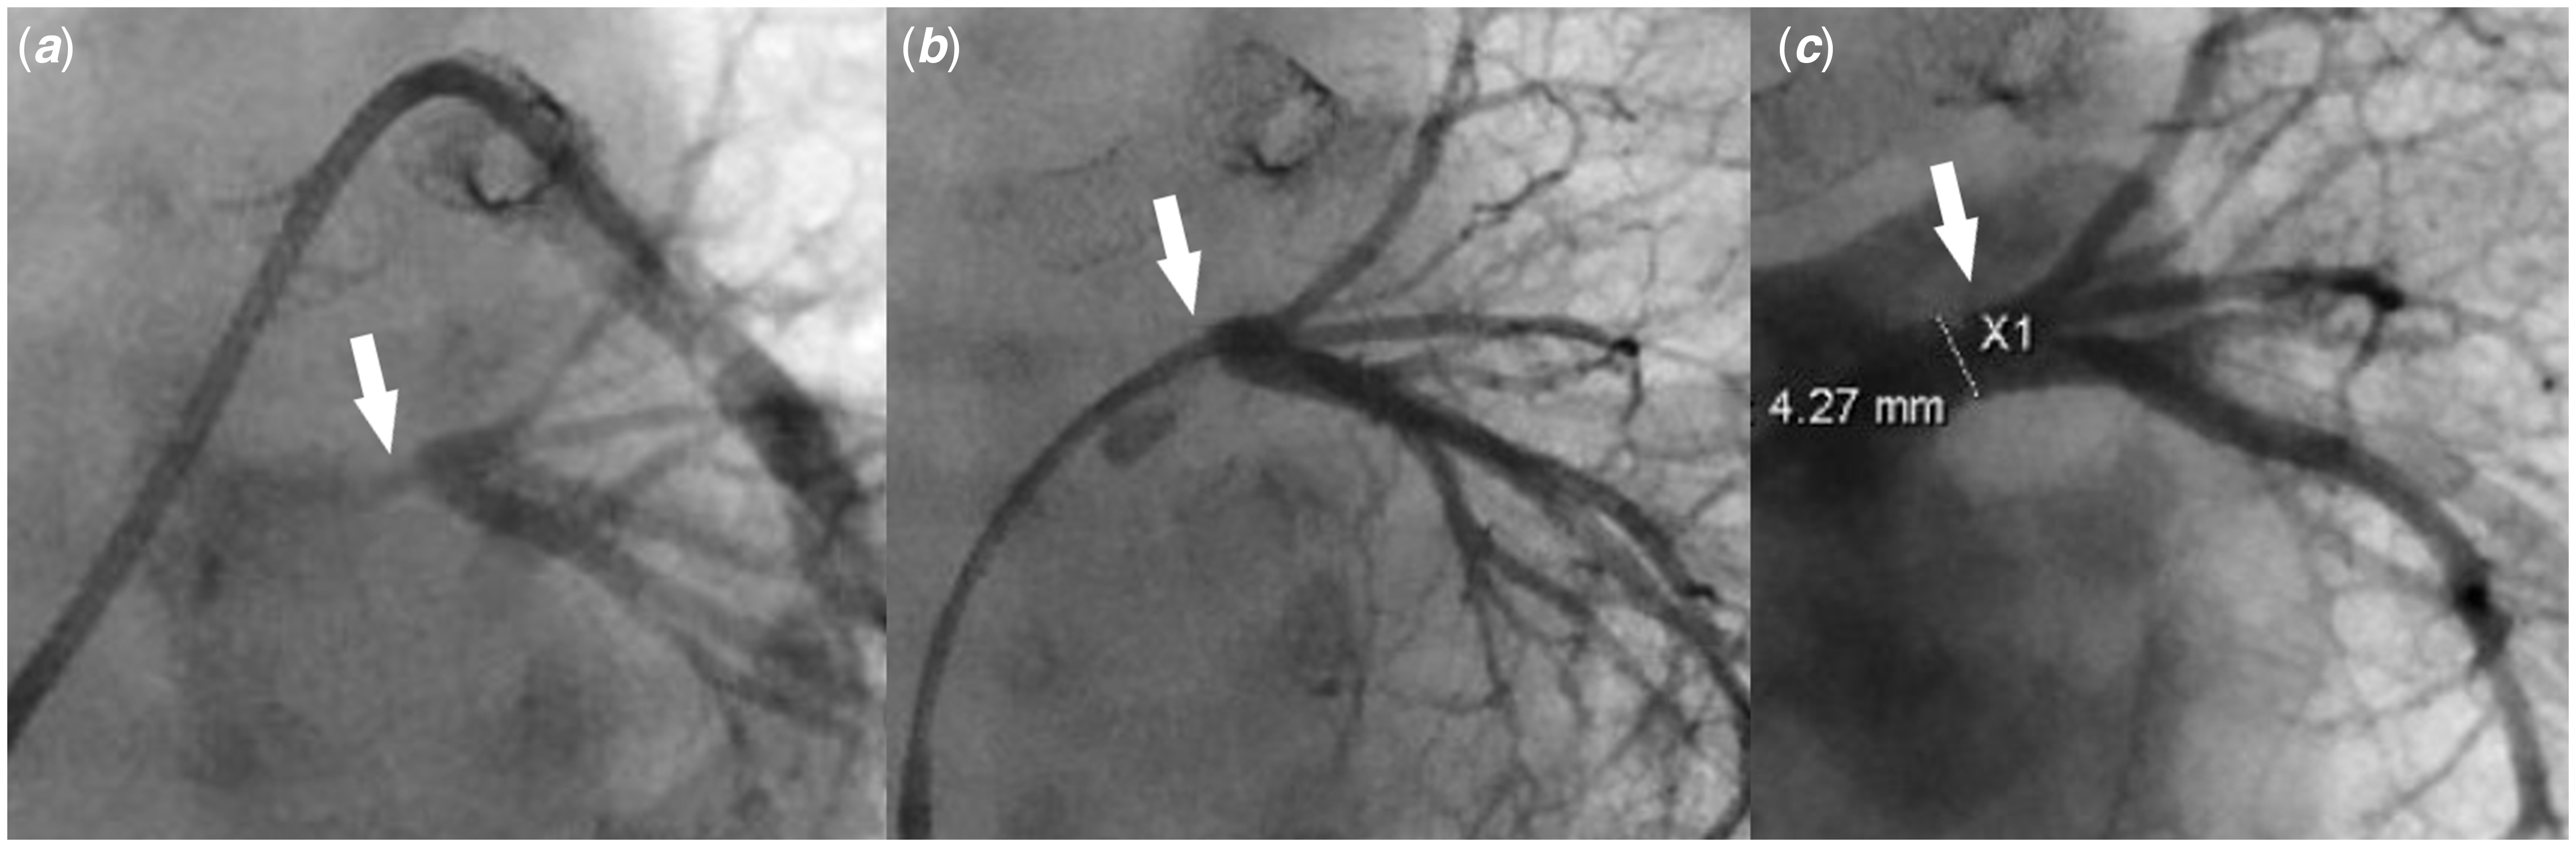

A 3-month-old male weighing 4.8 kg was born with truncus arteriosus, interrupted aortic arch, and persistent left superior caval vein draining into the right atrium via what was initially thought to be fully roofed coronary sinus. He underwent surgical repair on day 10 of life consisting of end-end arch repair, ventricle septal defect closure, and placement of right ventricle-pulmonary artery homograft. Immediately after repair, stents were placed in the proximal right and left pulmonary arteries due to severe stenosis. Due to the persistent low oxygen saturation (in the mid-80s), a bubble study echocardiogram was performed which revealed that the coronary sinus was partially unroofed. A cardiac CT scan 3 weeks post-repair showed stenosis of the left pulmonary artery proximal to the stent, as well as normal size common right and common left pulmonary veins. An echocardiogram at 3 months of age revealed increased estimated right ventricle systolic pressure, increased flow velocity in the branch pulmonary arteries, flow turbulence in the common left pulmonary vein, no atrial septal defect, dilated coronary sinus ostium, and unroofed distal coronary sinus with the unroofed segment measuring 7 mm in length (Figs 1 and 2). He was taken to the cardiac catheterisation lab for possible intervention on the stented pulmonary arteries. The right femoral vein and artery were accessed using a 5-Fr sheath and a 20-gauge catheter, respectively. Haemodynamic measurements showed elevated distal pulmonary artery pressure with a mean of 26 mmHg and an elevated calculated pulmonary vascular resistance (9.8 Wood units × m2). Balloon angioplasty was then performed in the right and left pulmonary artery stents, along with the placement of an additional stent in the proximal left pulmonary artery to treat the aforementioned stenosis. The left pulmonary artery wedge angiogram showed severe ostial stenosis of the common left pulmonary vein (Fig 3A). Attempts to cross the atrial septum (probing the foramen ovale) were unsuccessful. Knowing the patient had an unroofed coronary sinus, we elected to attempt left atrial access via the coronary sinus. A coaxial system consisting of a 5-Fr JR4 guide catheter (Medtronic), 4-Fr JR 2 catheter (Cook Medical), and 0.035" angled glide wire (Terumo) was inserted through the right femoral vein sheath into the coronary sinus. The catheters were oriented superiorly and rightward. The wire was advanced to cross the coronary sinus into the left atrium. The catheters were then advanced over the wire inside the left atrium. The angled glide wire was exchanged for a 0.014" Choice wire (Boston Scientific). The catheters were turned toward the common left pulmonary vein. The Choice wire was manipulated to cannulate the common left pulmonary vein. The JR2 catheter was then advanced over the wire into the left lower pulmonary vein (Fig 2). Pressure measurements revealed a gradient of 16 mmHg across the stenosis. Angiograms showed severe stenosis of the left pulmonary vein just distal to the ostium and the normal pulmonary vein measuring 4.2 mm (Fig 3B). The Choice wire was exchanged for a stiffer coronary wire [0.014" Asahi Grand Slam wire (Abbott)] to provide more support for pulmonary vein stent placement. Then, the 5-Fr guide catheter was advanced over the JR2 catheter inside the vein and the JR2 catheter was removed. A 4 × 8 mm Synergy everolimus-eluting stent (Boston Scientific) was advanced over the wire inside the guide catheter and centred across the stenotic portion. The stent was deployed by inflating the balloon to 18 atmospheres (the rated burst pressure) to achieve a stent diameter slightly larger than 4 mm to match the normal distal pulmonary vein segment. Angiography revealed a well-positioned stent (Fig 3C). Pressure measurement showed no gradient across the stent. No significant improvement in his oxygen saturation was noticed at the end of the procedure. The patient was discharged home on the same home dose of aspirin and started on Sildenafil. Over the next few weeks following the procedure, his oxygen saturation has increased to 93–95%.

Figure 3. (a) Pulmonary artery wedge angiogram shows severe left common pulmonary vein ostial stenosis (white arrow). ( b) Left common pulmonary vein angiogram shows severe left common pulmonary vein stenosis (white arrow) with well-developed distal pulmonary vein branches. ( c) Left pulmonary vein angiogram post-stent placement shows a well-positioned stent (white arrow) inside the left common pulmonary vein with good expansion, resolution of the stenosis, and no evidence of vascular injury or jailing of the segmental left pulmonary veins.